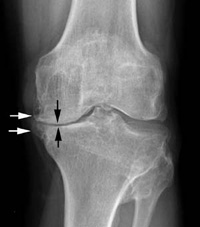

X-rays can show the extent of joint deterioration, including narrowing of joint space, thinning or erosion of bone, excess fluid in the joint, and bone spurs or other abnormalities. They can help the doctor distinguish various forms of arthritis.

(Reproduced with permission from Griffin LY(ed): Essentials of Musculoskeletal Care 3rd edition. Rosemont, IL. American Academy of Orthopaedic Surgeons. 2005.)